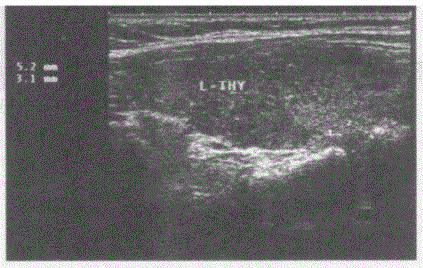

临床资料:男,49岁,常规体检。超声综合描述:甲状腺左叶上、下极后方可见大小均为0.5cm×0.3cm中等回声,边界清晰,形态规则,内回声均匀。 ...

问题 临床资料:男,49岁,常规体检。 超声综合描述:甲状腺左叶上、下极后方可见大小均为0.5cm×0.3cm中等回声,边界清晰,形态规则,内回声均匀。 超声提示: